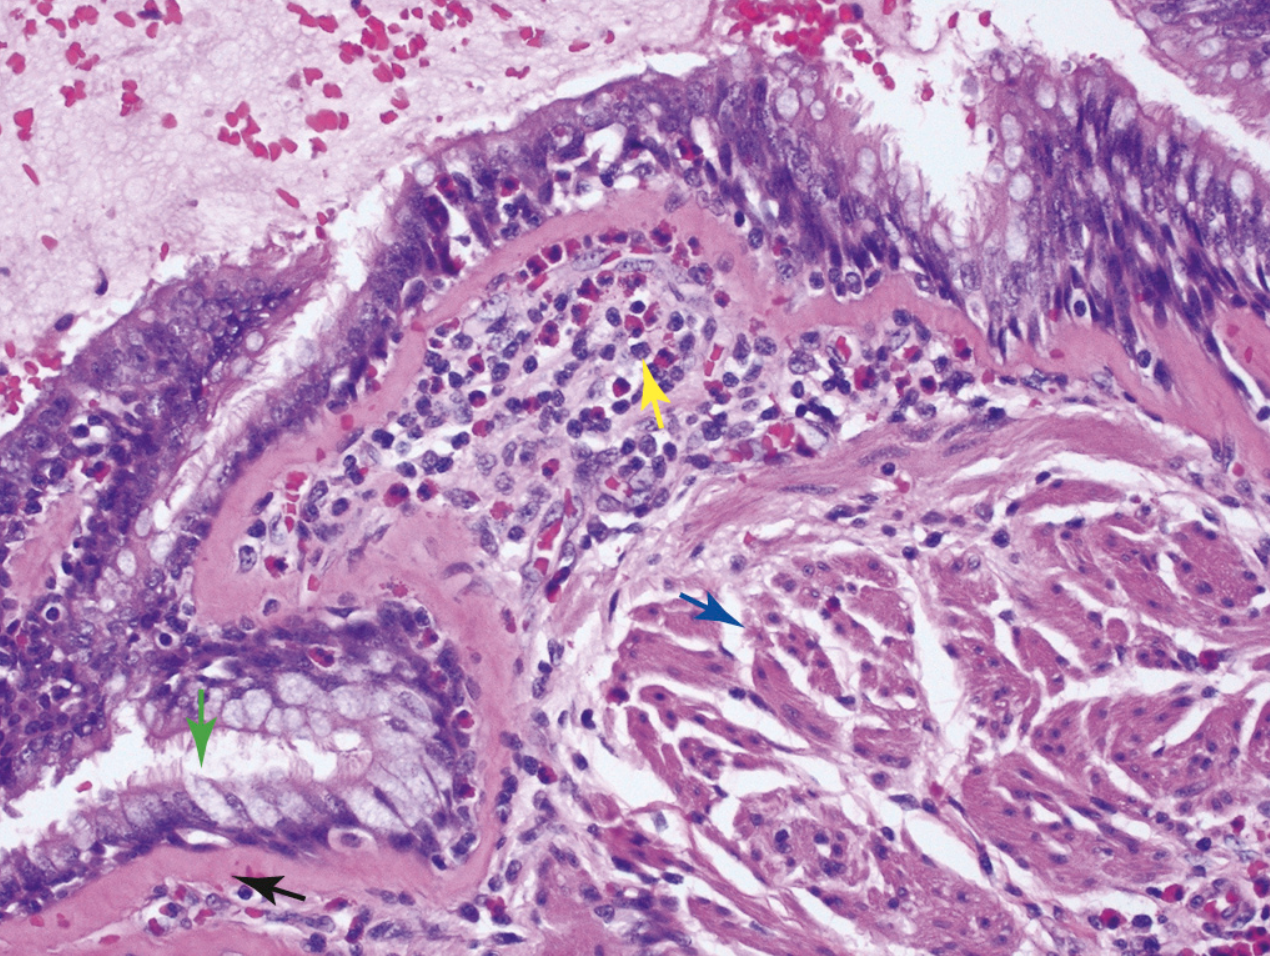

¿Qué está señalando la flecha verde?

Hiperplasia de las células calciformes

¿Qué está señalando la flecha azul?

Hipertrofia muscular

¿Qué está señalando la flecha negra?

Fibrosis subyacente a la membrana basal

¿Qué está señalando la flecha amarilla?

Inflamación eosinofílica

Asma

Solo ver